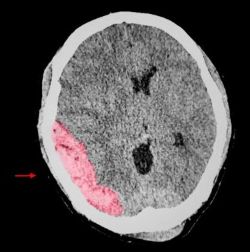

Traumatic brain injury occurs when an external force disrupts the normal function of the brain. It can result from direct head trauma, sudden acceleration or deceleration forces, or penetrating injuries such as gunshot wounds. A brain CT scan of a patient with traumatic brain injury showing large lens shaped epidural hemorrhage (EDH). Image Credit: Sopone Nawoot from Getty Images via Canva.com.

A hematoma is a collection of blood outside the brain’s blood vessels, which can form within or around the brain following trauma. Hematomas are classified based on their location, including epidural, subdural, and intracerebral hematomas. Depending on the severity, hematomas can cause increased pressure on the brain, leading to severe headaches, loss of consciousness, vomiting, and neurological deficits. Large hematomas may require surgical drainage to prevent further brain damage, while smaller ones may be monitored closely to ensure they do not expand and worsen over time.